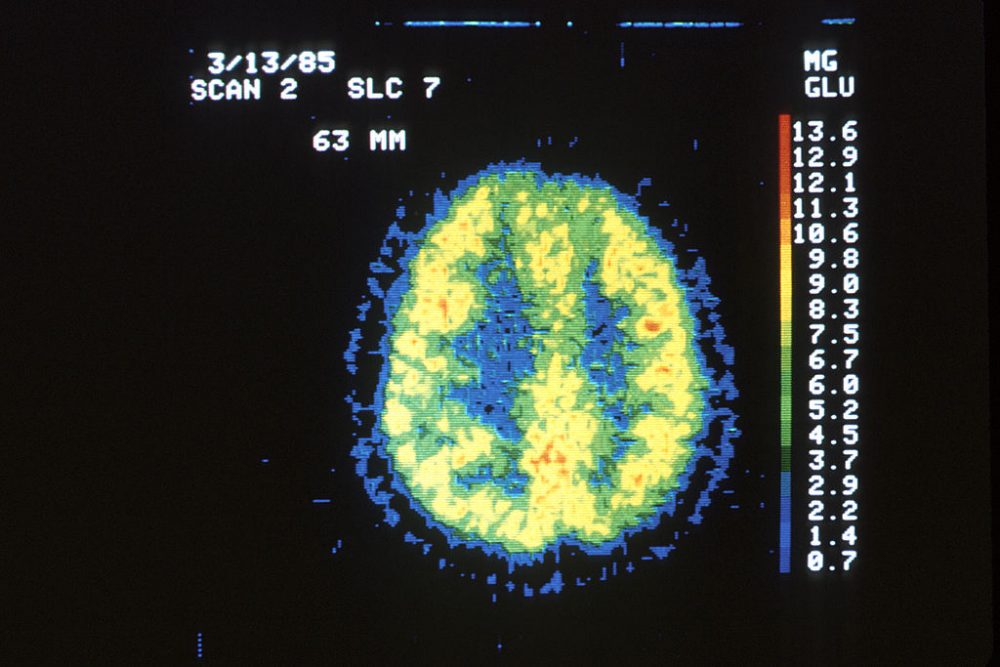

For years, psychiatric researchers have explored the links between genes and mental illness. Now, a new study in the journal Science analyzing the DNA of over a million people illuminates just how blurred the lines are between genetic risk factors for seemingly different brain disorders. The results add to hopes that studying the genetics of psychiatric disorders could lead to more effective treatments.